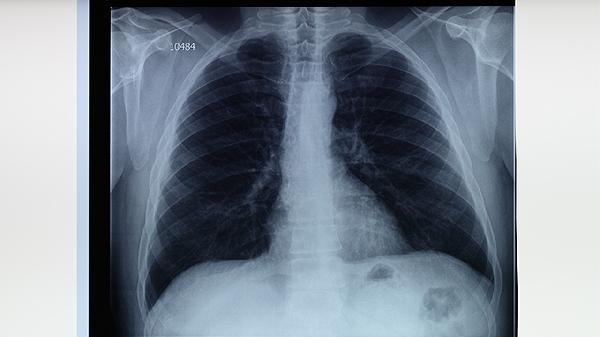

肺結(jié)核可能引起肺源性心臟病、結(jié)核性腦膜炎、腸結(jié)核、骨關(guān)節(jié)結(jié)核、腎結(jié)核等并發(fā)癥。肺結(jié)核是由結(jié)核分枝桿菌感染引起的慢性傳染病,若未及時(shí)規(guī)范治療,病原體可能通過血液或淋巴系統(tǒng)擴(kuò)散至全身其他器官。

長期肺結(jié)核導(dǎo)致肺組織廣泛纖維化,可能引發(fā)肺動(dòng)脈高壓,增加右心負(fù)荷形成肺心病。患者可能出現(xiàn)呼吸困難、下肢水腫等癥狀。治療需聯(lián)合抗結(jié)核藥物如異煙肼片、利福平膠囊,并配合氧療改善心肺功能。

結(jié)核菌經(jīng)血行播散至腦膜可引起致命性炎癥,表現(xiàn)為持續(xù)頭痛、頸項(xiàng)強(qiáng)直和意識障礙。確診需通過腦脊液檢查,治療需使用能透過血腦屏障的藥物如吡嗪酰胺片、鏈霉素注射液,療程通常需12個(gè)月以上。

吞咽含菌痰液或血行感染可能導(dǎo)致回盲部結(jié)核,典型癥狀為腹痛、腹瀉與腹部包塊。腸鏡檢查可見潰瘍性病變,治療需全程使用乙胺丁醇片等抗結(jié)核藥物,嚴(yán)重腸梗阻時(shí)需手術(shù)干預(yù)。

脊柱結(jié)核最常見,表現(xiàn)為椎體破壞和冷膿腫形成,可能壓迫脊髓導(dǎo)致截癱。X線可見椎間隙狹窄,治療需聯(lián)合異煙肼片與外科清創(chuàng)術(shù),臥床制動(dòng)3-6個(gè)月有助于病灶修復(fù)。

血行感染可導(dǎo)致腎實(shí)質(zhì)結(jié)核性空洞,出現(xiàn)無菌性膿尿和膀胱刺激征。靜脈腎盂造影可見腎盞蟲蝕樣改變,治療需長期服用利福平膠囊,嚴(yán)重腎損毀需行腎切除術(shù)。